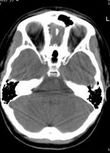

雙側上頜竇炎就是鼻竇中的上頜竇炎,區別於普通的單側上頜竇炎 ,主要為雙側鼻竇發炎、前後鼻滴涕,有時鼻分泌物隨頭部姿勢改變而流出,患者自訴痰多且臭,分泌物為粘液膿性或膿性。患者常有頭昏或膿性。患者常有頭昏頭痛,記憶力減退,思想不能集中。但有一部分患者忘記了自己的症狀,及至鼻部檢查才發現有慢性上頜竇炎。

雙側上頜竇炎急性發病者,要注意很好地休息。慢性者要增強體質,避免過度疲勞,吃富於營養的食物。其次,對上頜竇局部的治療,是促進鼻竇通氣和引流,可用有血管收縮和黏膜消腫作用的藥物,如1%麻黃素等。還可以加入各種消炎抗感染的藥物滴鼻,如卡那黴素、呋喃西林等。也可以用局部熱敷、紅外線照射,以利促進血液循環的改善。千柏鼻炎片,藿膽片、辛夷合劑、蒼耳子散等,也有些效果。必要時,可作上頜竇穿刺手術,洗除上頜竇腔內的粘液膿涕。同時,再注射各種抗菌藥物,如青黴素、鏈黴素、卡那黴素等。屢次穿刺無效的,可做上頜竇根治手術,清除或刮除上頜竇腔內的各種病變組織,改善它的通氣及引流情況

在急性鼻竇炎向慢性鼻竇炎轉化過程中,鼻竇中的細菌也會產生變化。研究對象為對抗生素治療無效的急性鼻竇炎患者,對其在首次發病的34~50天內進行動態細菌培養研究。首次抽吸培養細菌為肺炎鏈球菌、流感嗜血菌和卡他莫拉菌。在此後的抽吸培養中除原有的細菌外又出現了厭氧菌,包括梭桿菌、紫單細胞菌和消化鏈球菌。而且分離出的需氧菌對抗生素的耐藥性逐漸增加。提示厭氧菌感染繼發於化膿性細菌感染。化膿性細菌感染為厭氧菌感染提供了厭氧條件(粘液的滯留、竇口的堵塞和缺氧)。 慢性鼻竇炎的致病菌變異很大,導致消炎類藥物治療很難取得效果。